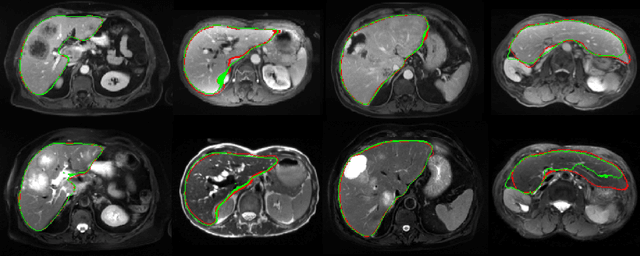

Abstract:We address the problem of multimodal liver segmentation in paired but unregistered T1 and T2-weighted MR images. We compare several strategies described in the literature, with or without multi-task training, with or without pre-registration. We also compare different loss functions (cross-entropy, Dice loss, and three adversarial losses). All methods achieved comparable performances with the exception of a multi-task setting that performs both segmentations at once, which performed poorly.